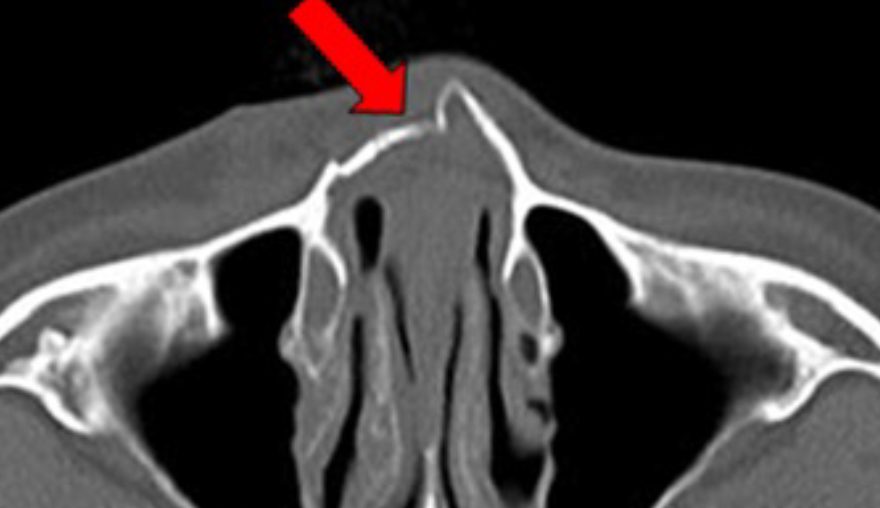

단순 함몰 골절